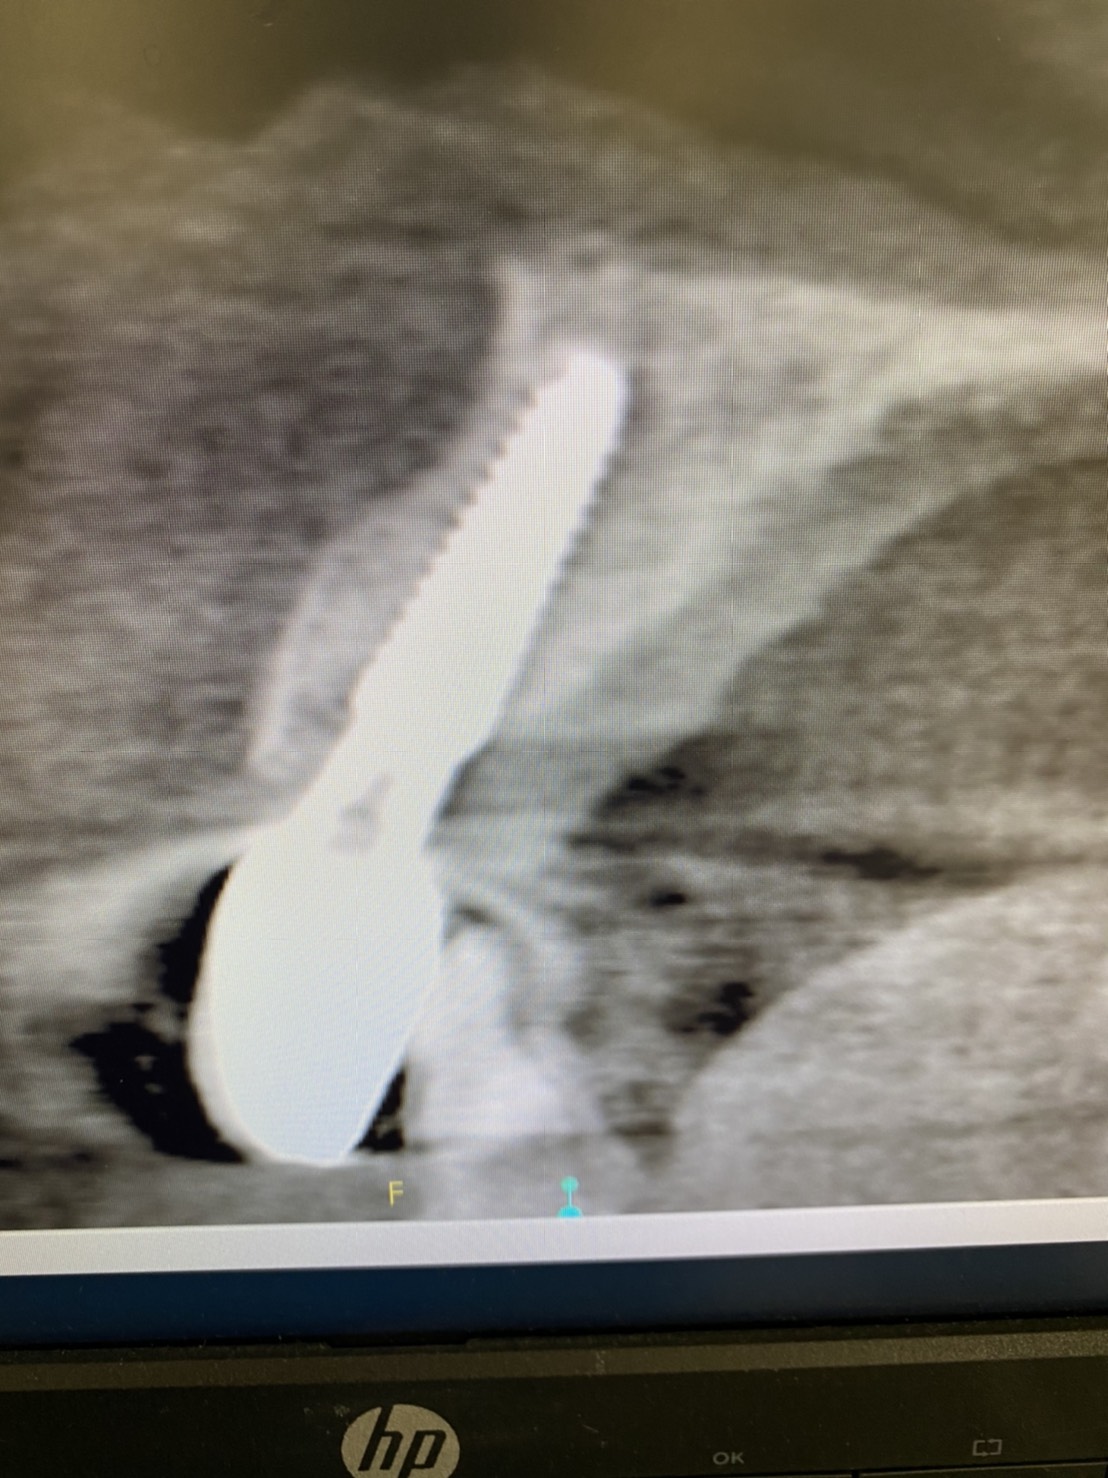

午後には、春にソケットシールド(12/4ブログにテクニックの説明あり)した方の上部構造をセットしました。

狙いどおりにバルコニー、頬側骨板が維持されNICEな結果に(^_^)v